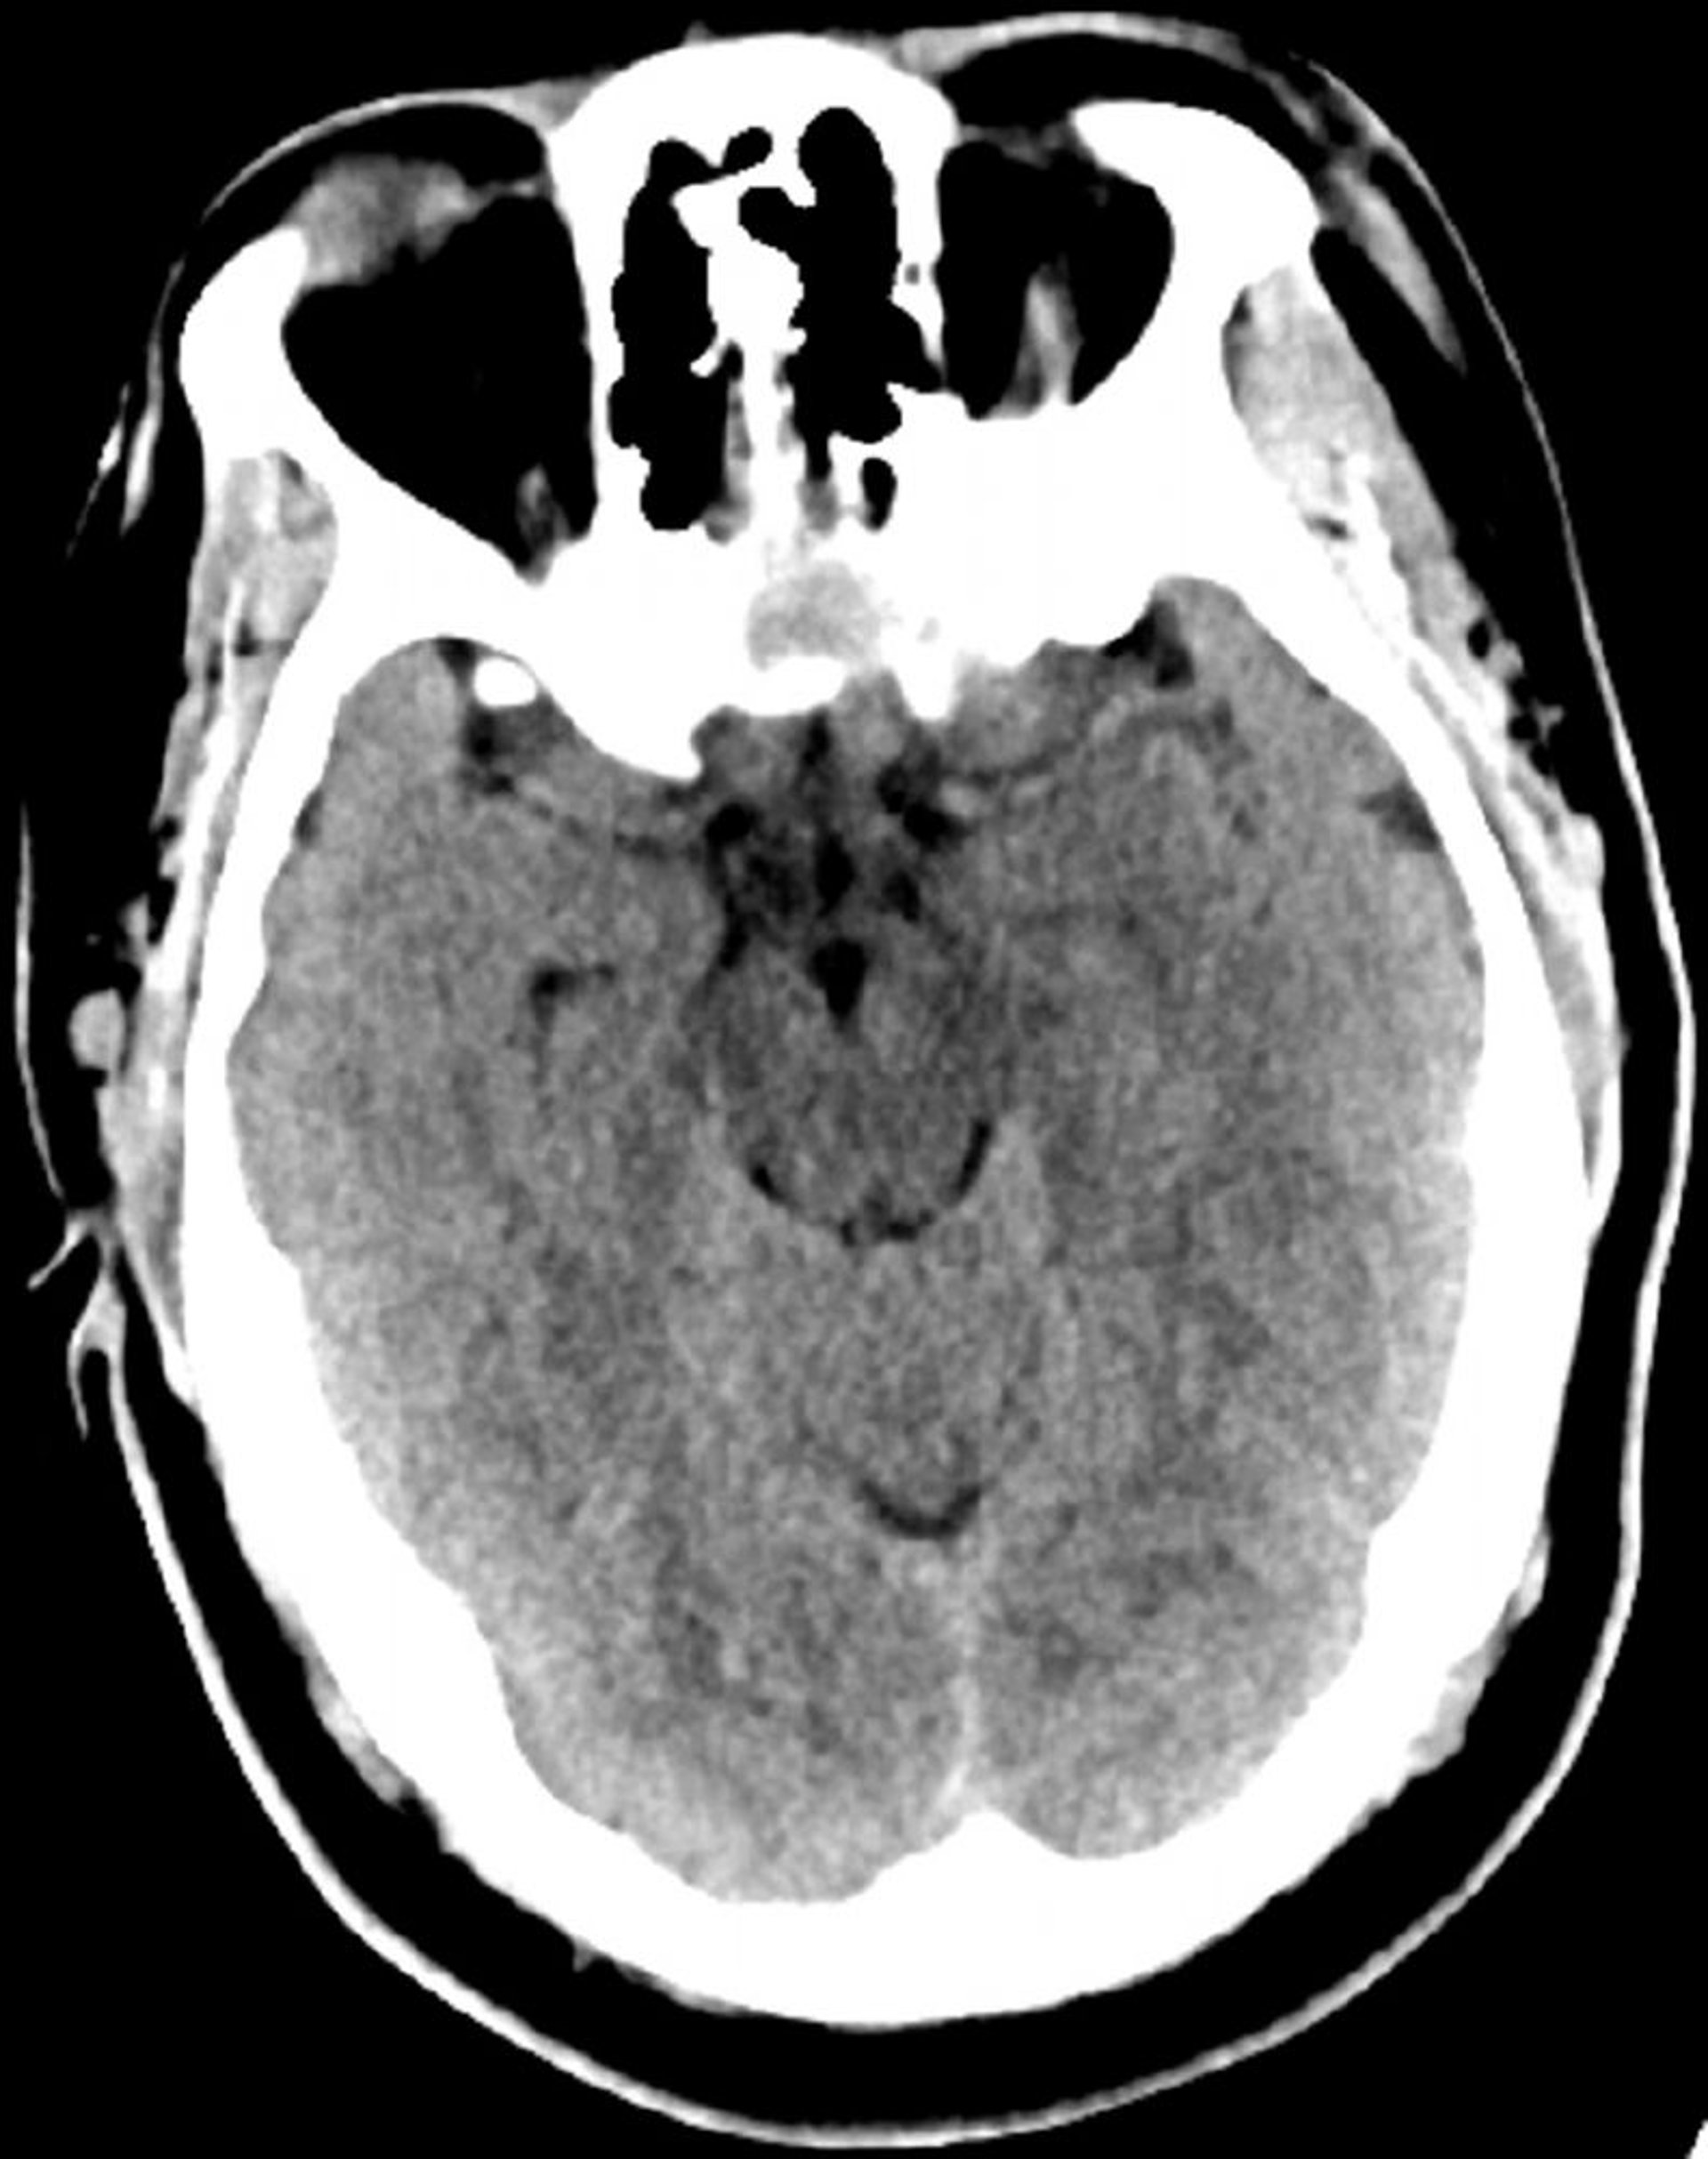

Tomografía computarizada craneal normal (adulto, 30 años)–diapositiva 6

Esta imagen es una tomografía computarizada craneal normal correspondiente a un adulto joven de 30 años de edad. No hay hemorragia o líquido intra- o extra axial. Se conserva la diferenciación gris-blanco. El tamaño ventricular y el patrón sulcal son normales.